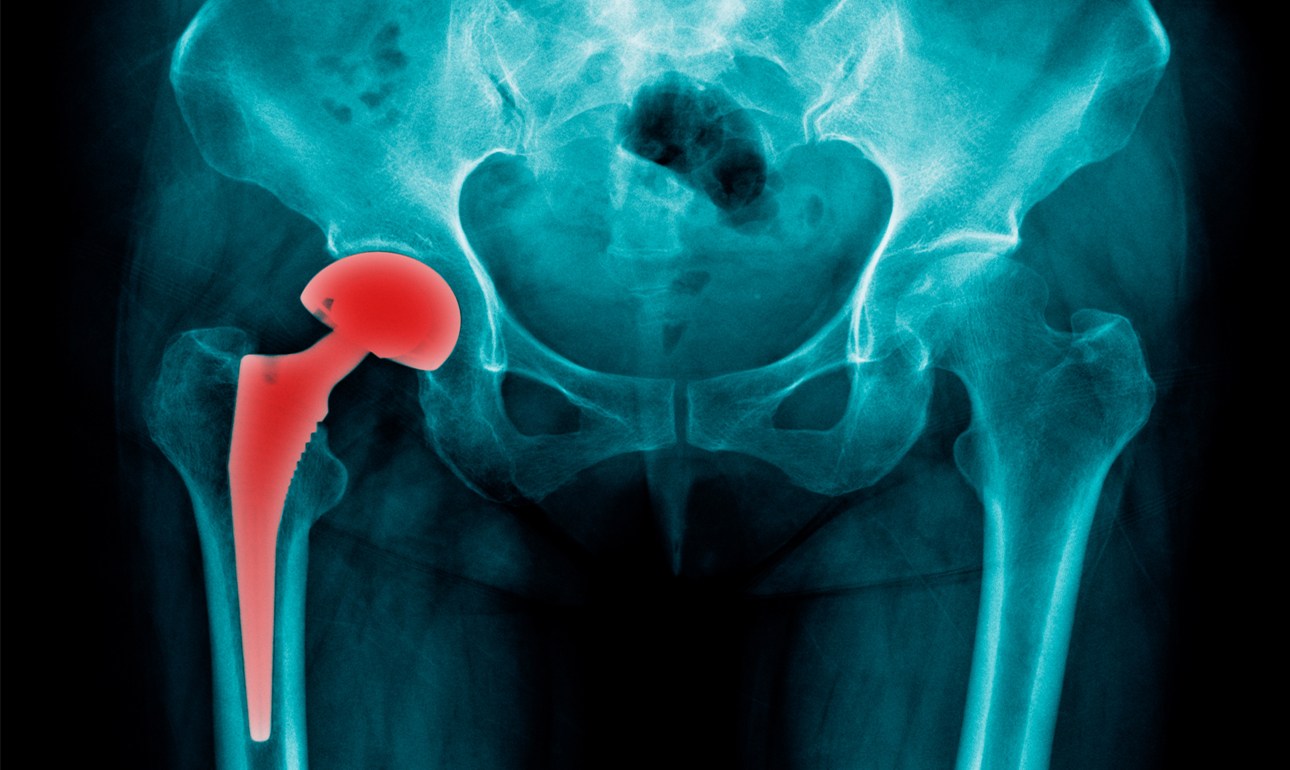

Πρόκειται για συσκευές ή τεχνητά εμφυτεύματα, όπως βηματοδότες, τεχνητά οστά (όπως ισχία), αντισυλληπτικά εμφυτεύματα, πλέγματα που χρησιμοποιούνται στη χειρουργική ή ακόμη και εμφυτεύματα για το στήθος.

– Τεχνητά ισχία και πλέγματα μήτρας πωλήθηκαν σε νοσοκομεία χωρίς να έχουν γίνει κλινικές δοκιμές.